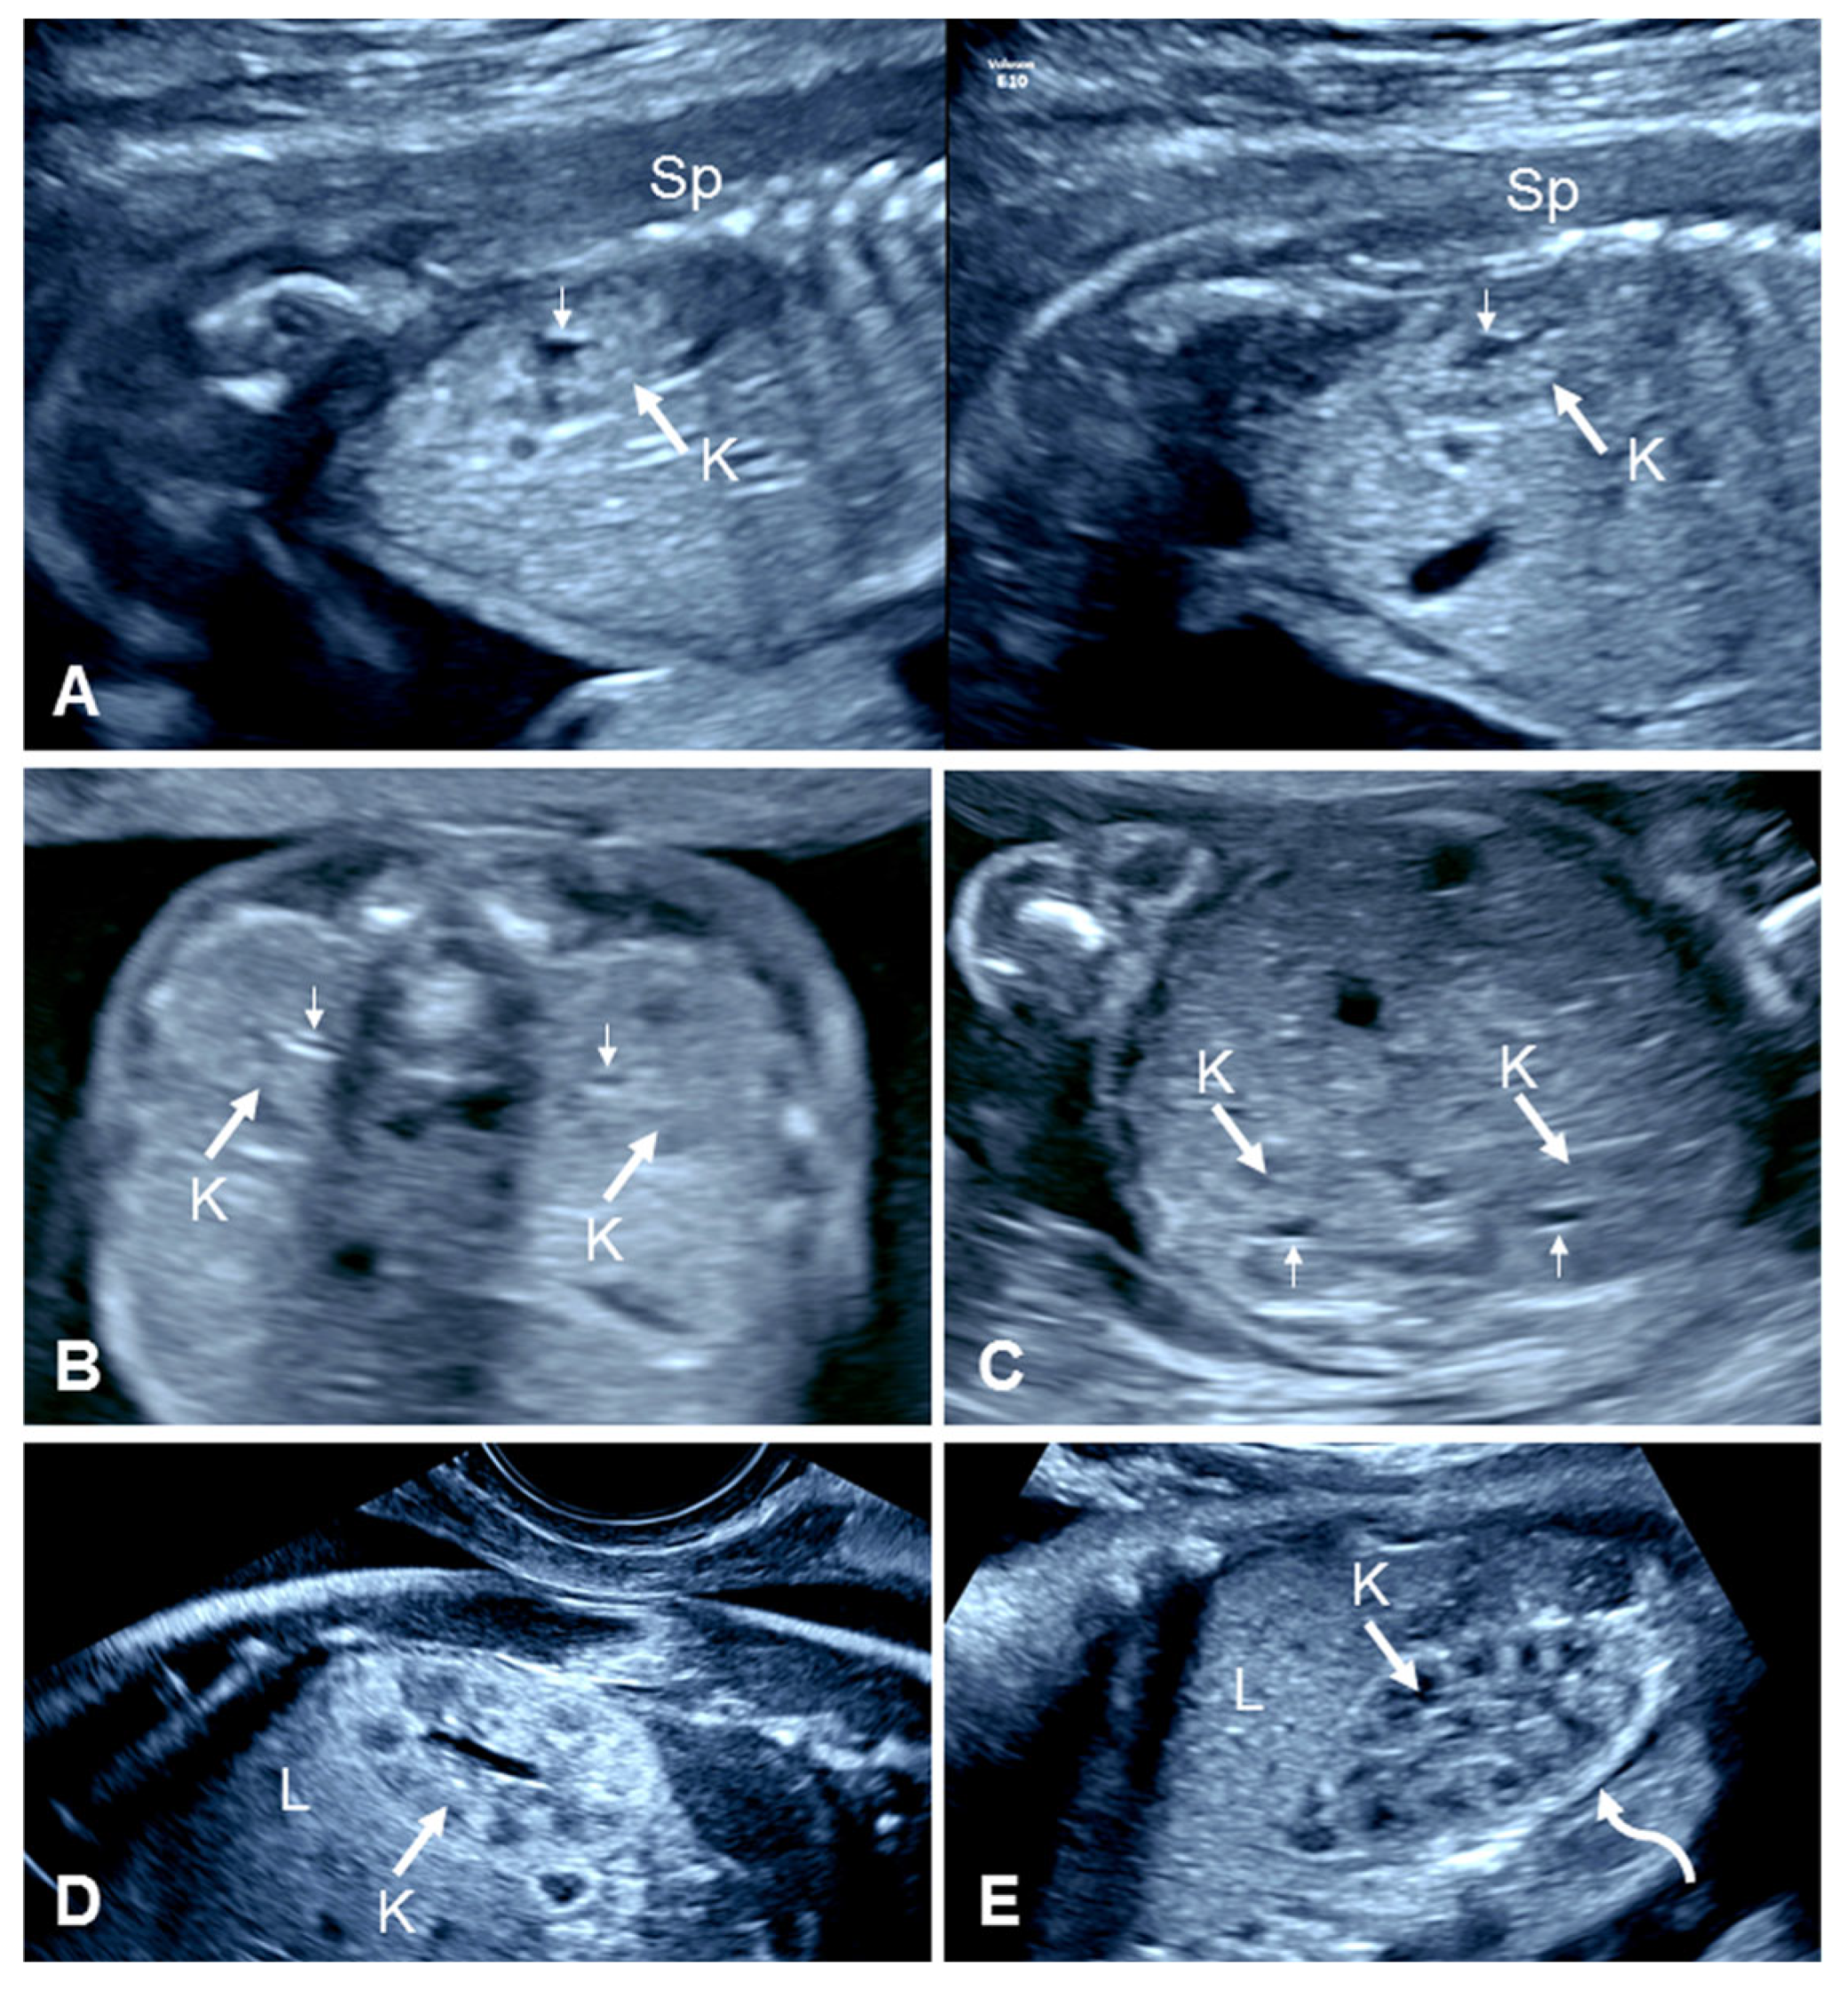

2.2.1. Empty Renal Fossa

2.2.2. ‘Lying Down’ Adrenal Gland

2.2.3. Contralateral Renal Hypertrophy

2.2.4. Absent Ipsilateral Renal Artery